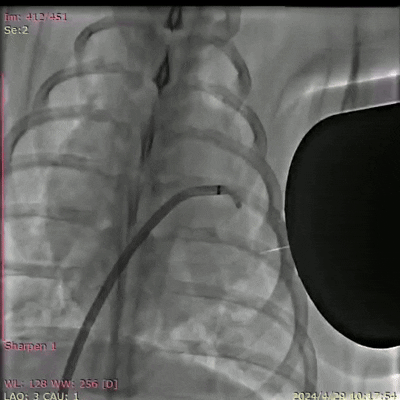

图3. DSA(数字减影血管造影)拍摄的巴马猪体内磁流体左心耳封堵实验过程(动图请看附件)。凯发k8官网供图